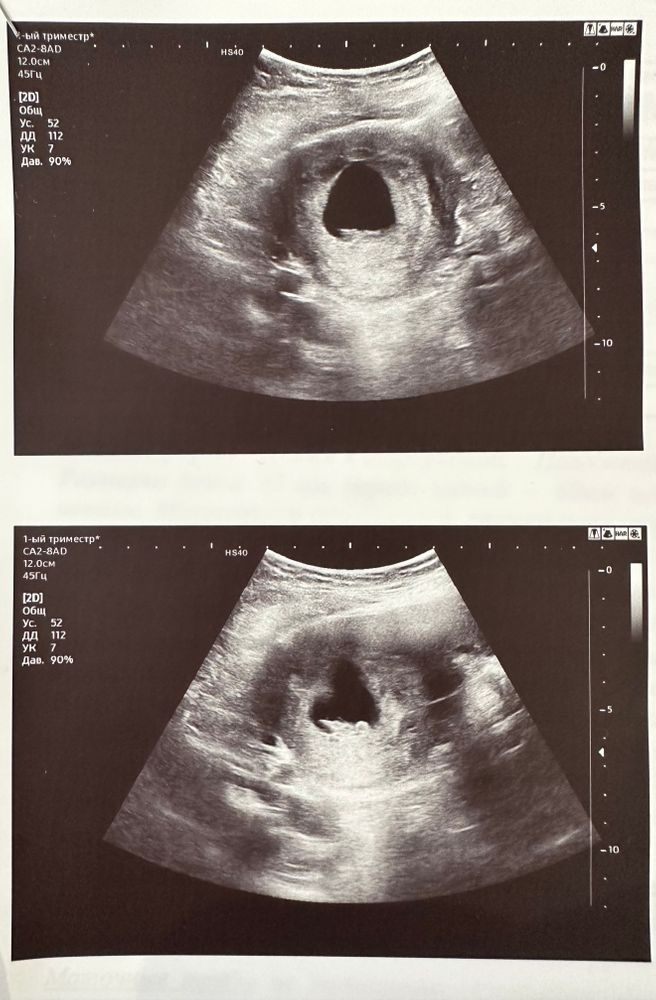

Первое УЗИ в 7,2 недели!

Девочки!была на УЗИ!по месячным 7,2 недели,по КТР-7,6!!кто разбирается-гляньте на фото!я уже всего боюсь-Б получилась в первый цикл после вакуума по причине ЗБ!

Это нормально. Узи всегда +-4 дня определяет срок

Ктр чуть опережает срок, чего же тут должно быть плохого? 🙌🙂